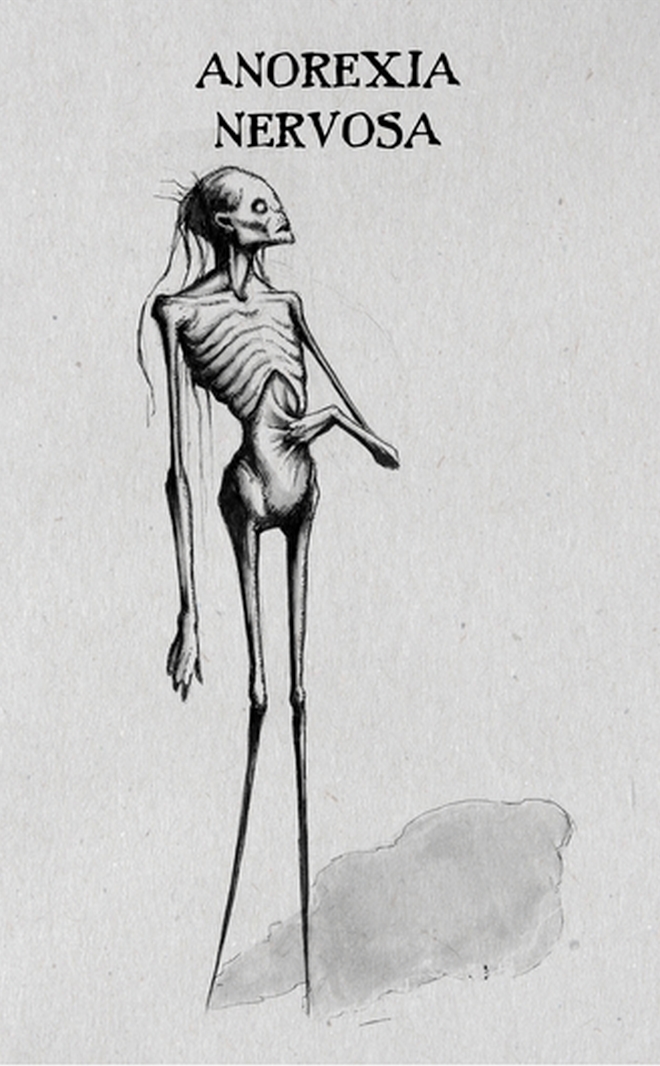

Ο Αμερικανός κομίστας μελέτησε τις ψυχικές ασθένειες και τις διαφορετικές εκφάνσεις τους και αποφάσισε να τις αποτυπώσει με το ιδιαίτερο στιλ του στο χαρτί. Παρουσίασε τις δημιουργίες αυτές στην πρωτοβουλία InkTober τον Οκτώβριο του 2016. Η απόδοσή τους προκάλεσε μεγάλη αίσθηση για τη ρεαλιστικότητά τους και έκαναν μέσω διαδικτύου τον γύρο του κόσμου.

Αξίζει να σημειωθεί ότι στο InkTober οι συμμετέχοντες σχεδιαστές καλούνται κάθε μέρα του μήνα (ή όσες ημέρες δίνουν το παρών) να φιλοτεχνούν από ένα τουλάχιστον σκίτσο με μελάνι. Ο Coss σχεδίασε συνολικά 18 σκίτσα για 18 διαφορετικές ψυχικές διαταραχές.

Ανορεξία